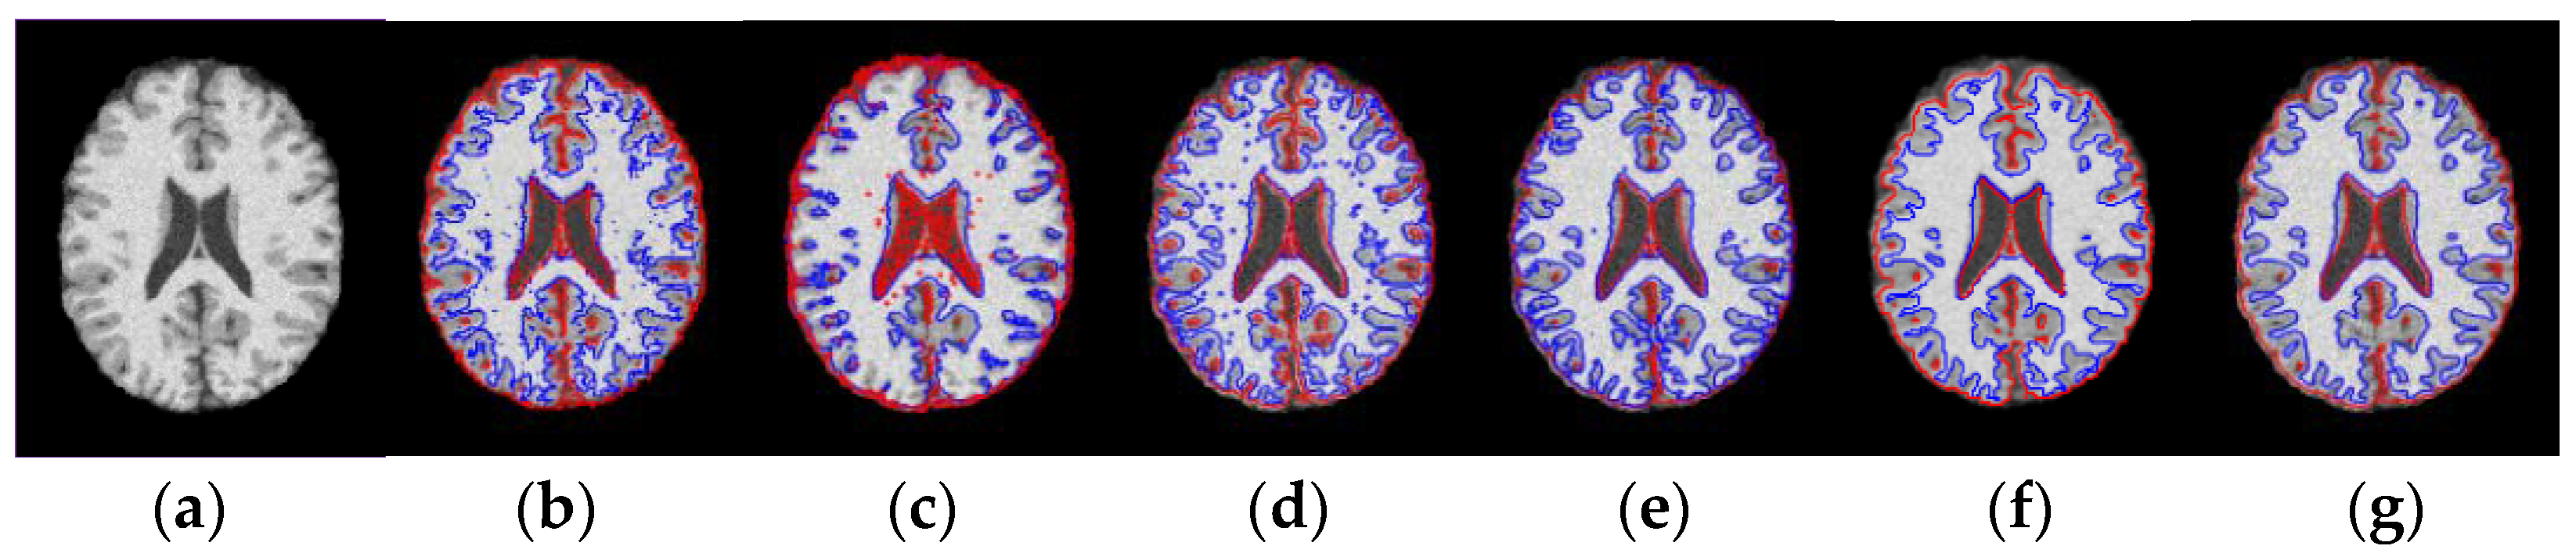

3.1. Results on Noisy Images

3.2. Results on Inhomogeneous Intensity Images